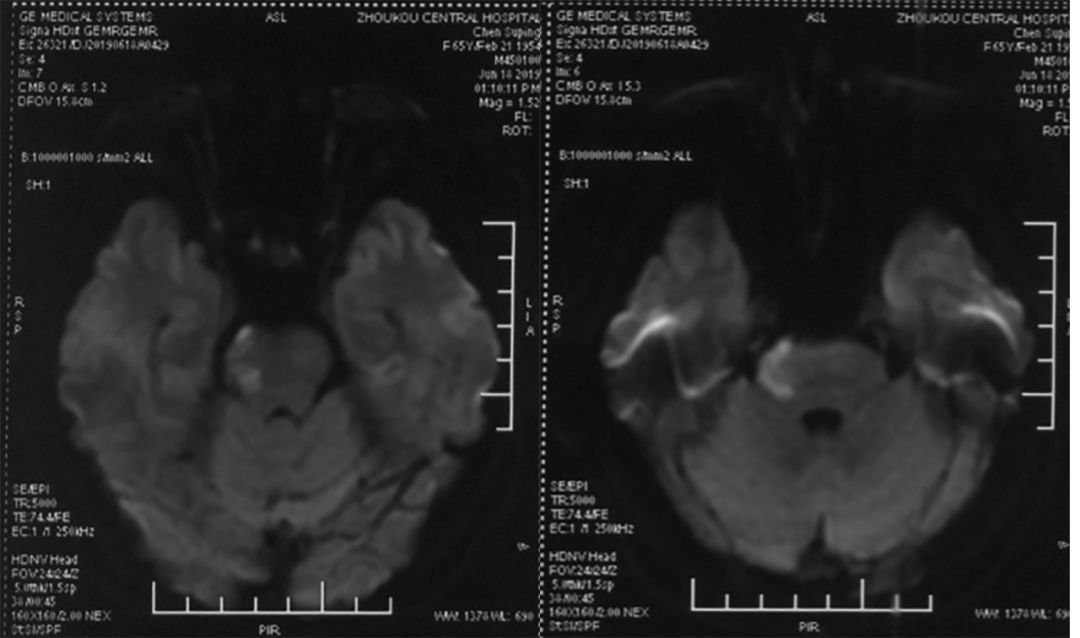

脑MRI (2019-6-18 ,*** 人民医院):右侧桥脑急性脑梗死(图1)。

图1